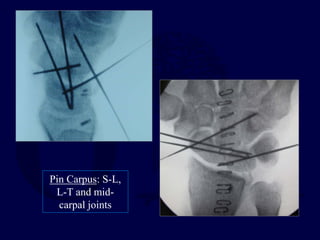

Pin Carpus: S-L,

L-T and mid-

carpal joints